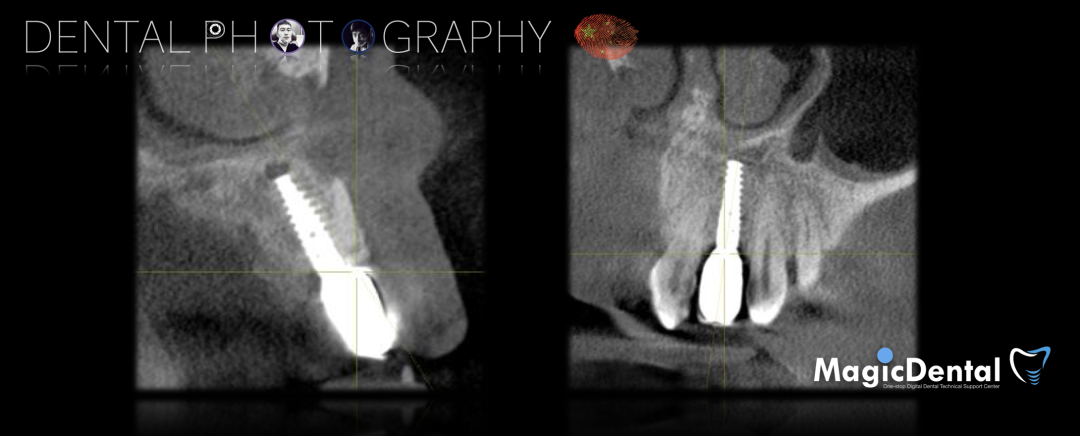

术前CBCT

22缺失,且牙槽骨唇颚侧宽度较窄,38,48近中阻生。

治疗计划:水平骨增量,拔除四区近中阻生智齿,下颌升支外斜线处取块状骨,移植骨块至受区(22唇侧),种植修复22缺失牙。

术后3个月CBCT及X线片。